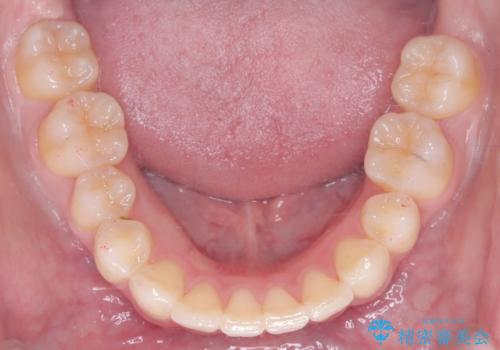

特に下顎の右方偏位に対しては、ワイヤーによる繊細なコントロールを行い、左右の咬合バランスを整えることに重点を置きました。2年半の治療期間を経て、突出していた前歯は理想的な位置に収まり、顎のズレも大幅に改善されました。

治療完了後は、お顔全体のバランスが整い、横顔のライン(Eライン)も美しく変化しました。審美ワイヤーを使用したことで、長期間の治療中もストレスを最小限に抑えながら、機能的で健康的な咬み合わせを獲得することができました。